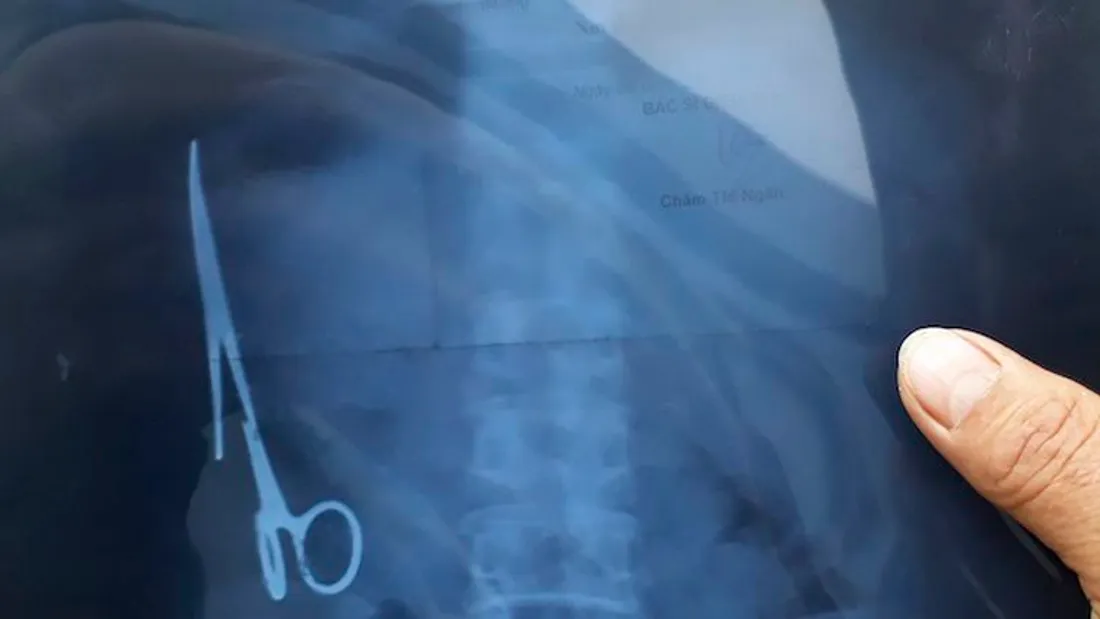

Au Bangladesh, une femme de 55 ans qui vivait depuis 20 ans avec des douleurs régulières à l’abdomen a découvert qu’une paire de ciseaux chirurgicaux était restée dans son corps après une ancienne opération. La quinquagénaire a été opérée avec succès le mardi 11 janvier 2022, afin de retirer le corps étranger.

En 2021, elle consulte un nouveau spécialiste qui lui propose de passer une radio. C’est une révélation. Bachena Khatun découvre qu’une paire de ciseaux chirurgicaux utilisée lors de son opération en 2002 était restée dans son corps pendant tout ce temps.